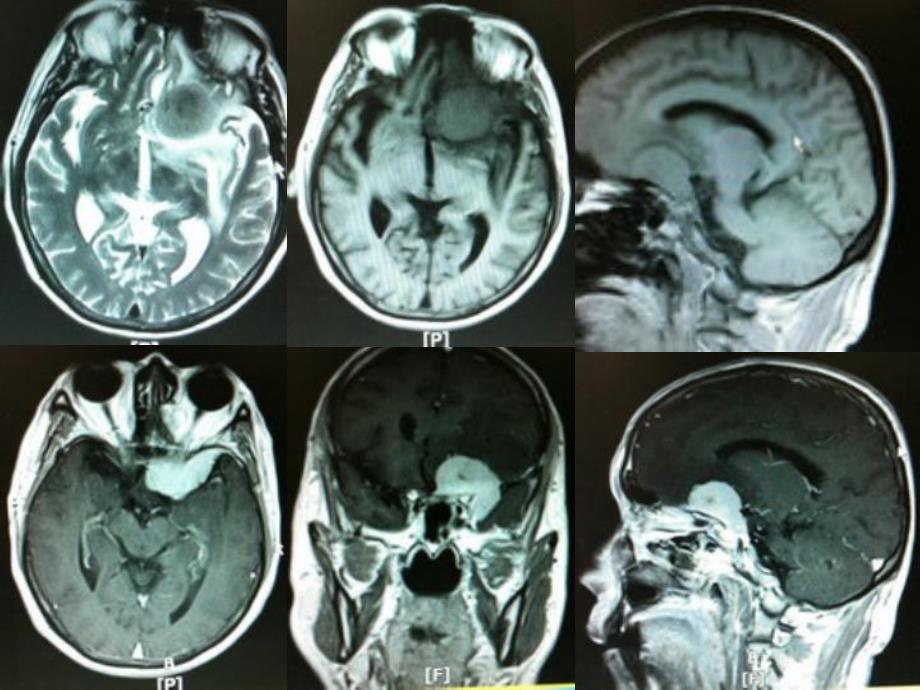

1、开颅手术中血管损伤的经验教训开颅手术中血管损伤的经验教训例1o 男性,64岁,因发作性神志不清,四肢抽搐1次而入院。体检神经系统无阳性体征术前检查o 心电图提示有异常Q波,心脏CTA提示冠脉前降支部分狭窄,心内科会诊认为无手术禁忌症。手术情况o 关颅前颈内动脉和大脑前中动脉用罂粟碱稀释液冲洗、浸泡5分钟,手术顺利完成。术后2小时神志转情,右侧肢体肌力4级。术后第一天o 神志朦胧,GCS12分,右侧肢体肌力1-2级,于是加大甘露醇剂量,应用尼膜同。术后第二天o 意识稍有好转,GCS13分,头颅CT复查提示左额颞深部脑水肿加重。术后第四天o GCS12分,扩容,并加用低右、丹参注射液治疗。此后病情

2、比较稳定,GCS13分,CT复查无明显改变。术后第7天术后第十三天o 意识急剧变差,GCS8分,右侧肢体肌力0级。即行左侧去骨瓣减压术,术后病情无明显改善。减压术后第二天o GCS6分,CT复查示左半球大片脑梗死,右顶颞脑梗死,最后家属放弃治疗,自动出院。例2o 女性,47岁,因头痛8年,突发肢体抽搐3天入院。体检无阳性体征。手术情况o 行开颅、皮层脑电监测、导航下海绵状血管瘤切除术,术中病灶切除顺利,但在切除病灶时由于静脉畸形出血,因此将畸形的静脉一并切除。在准备关颅时,发现整个术野的脑组织逐渐出现淤血、出血,类似于正常灌注压突破现象,只得切除部分出血的脑组织后关颅。o 术后1小时神志转清,

3、右上肢肌力4级,右下肢肌力1级。术后第一天o 神志清楚,重度运动性失语,右上肢远端肌力2级,近端和右下肢肌力0级,予以保守治疗。术后第二天o 神志清楚,重度运动性失语,右侧肢体肌力0级,CT复查血肿无增大,水肿明显。术后第五天o 右下肢肌力1-2级,右上肢肌力1级。术后第六天 失语有所好转,中度失语,右上肢远端肌力3级,近端肌力0级,右下肢肌力2级。术后第八天 情绪低落,焦虑,中度运动性失语,上肢肌力1级,下肢2级。术后第十二天,o 轻度失语,肌力仍为1-2级。术后22天o 轻度失语,情绪好转,右上下肢体肌力已达3级,术后26天o 右上肢肌力4级,下肢肌力3级。术后29天o 右上肢肌力4级,下

4、肢肌力4-级,搀扶下能行走。出院继续康复治疗。经验教训:例1动脉保护o 病人的手术指征、手术操作、术中处理和术后治疗应该没什么问题。o 术中已经注意到血管的保护和应用血管扩张剂,术后已扩容治疗。o 主要是病人年龄较大,本身有血管的基础疾病,在手术的刺激下发生脑梗死。o 术前除了要考虑到手术的一般并发症外,还要特别注意和防范脑血管意外(梗塞或脑出血)的发生,尤其是术前谈话时要与家属特别强调,做好医患沟通,争取患者家属的理解。经验教训:例2静脉保护o 问题的关键是静脉畸形的处理,其髓静脉虽然是畸形血管,但它还有正常静脉的功能,其周围的血液都通过此静脉回流,如果没有出血,手术应该尽量保留而不予切除。o 思想上没有高度重视,该病例就是由于认为畸形血管较小,以为即使切除后也只是局部的水肿而已,根本没想到会有如此严重的灌注压突破,因此才会切除畸形静脉而导致严重后果。经验教训o 手术应该从畸形的静脉前方入路,避开畸形的静脉丛切除海绵状血管瘤,即使有周边的畸形静脉出血,也应该压迫止血而不切除静脉畸形。小结o 综上所述,颅内手术除了病灶本身的切除、脑组织的保护外,还应该重视血管保护,无论是动脉还是静脉,都要尽可能地避免损伤和骚扰刺激,真正做到微侵袭,最大程度地保护脑功能。